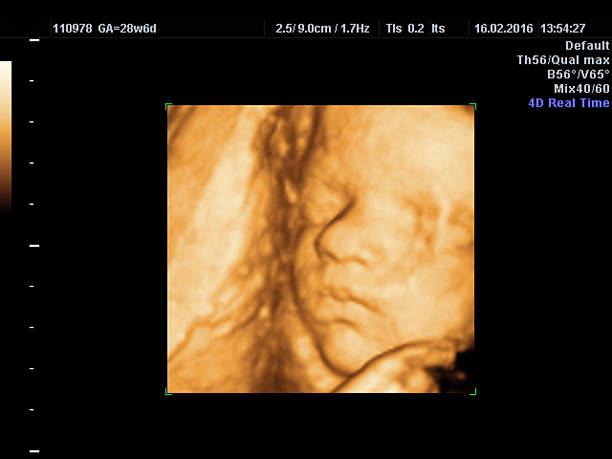

شكل الجنين في الشهر الاول

بمجرد معرفتك بخبر الحمل، يبدأ لديكِ التشوق لمعرفة كل تطور لجنينك لحظة بلحظة، ابتداءً من مراحل نموه وحجمه وشكله. من الممكن أن تلاحظي أنه في أول أسبوعين من الحمل، لا وجود للجنين بعد ولا توجد له صورة في الموجات فوق الصوتية، حيث أن شكل الجنين في الشهر الاول عبارة عن بذرة صغيرة، لكن مع مع بداية الأسبوع الثالث من الشهر الأول يمكن التعرف على شكل الجنين بالصور، حيث يكون على هيئة كمثرى. في نهاية الشهر الأول يكون الجنين قد بدأ في التكوين، كما يبدأ تكوين المشيمة المسؤولة عن التغذية، كيس الحمل يحيط بالطفل، وفي هذا المقال سوف نعرفكِ سيدتي على شكل الجنين في الشهر الاول و حجم الجنين في الشهر الاول، فتابعي معنا حتى النهاية.

حجم الجنين في الشهر الاول

قد تتساءلين عن حجم الجنين في الشهر الاول، لكن في البداية لا بد أن ننوه أنه في هذه المرحلة ينقسم الجنين إلى ثلاث طبقات من الخلايا، الطبقة الأولى يتكون فيها الجهاز العصبي والعين والشعر والجلد، و الطبقة الوسطى، يتكون فيها القلب والأوعية الدموية والعظام والعضلات والجهاز التناسلي، و الطبقة الأخيرة، تتكون فيها المعدة والأمعاء والرئتين وباقي أعضاء الجسم. يكون حجم الجنين في الشهر الاول بطول 0.254 مم. و وزن 1.13 جم.